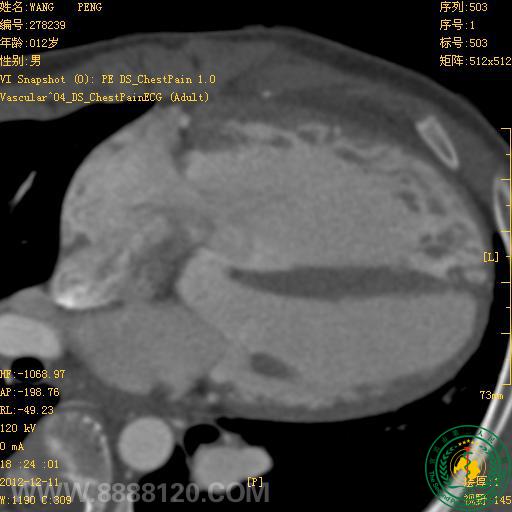

我院新双源CT在先天性心脏病中的首例应用

宜宾市第二人民医院 图文